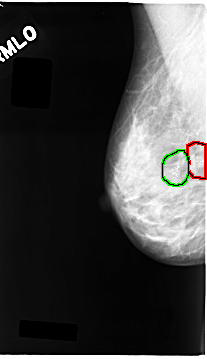

C_0063_1.RIGHT_MLO

RIGHT_MLO LINES 4664 PIXELS_PER_LINE 2680 BITS_PER_PIXEL 12 RESOLUTION 50 OVERLAY

FILE: C_0063_1.RIGHT_MLO.OVERLAY

TOTAL_ABNORMALITIES 2

ABNORMALITY 1

LESION_TYPE CALCIFICATION TYPE PLEOMORPHIC DISTRIBUTION CLUSTERED

ASSESSMENT 5

SUBTLETY 5

PATHOLOGY MALIGNANT

TOTAL_OUTLINES 1

BOUNDARY

ABNORMALITY 2